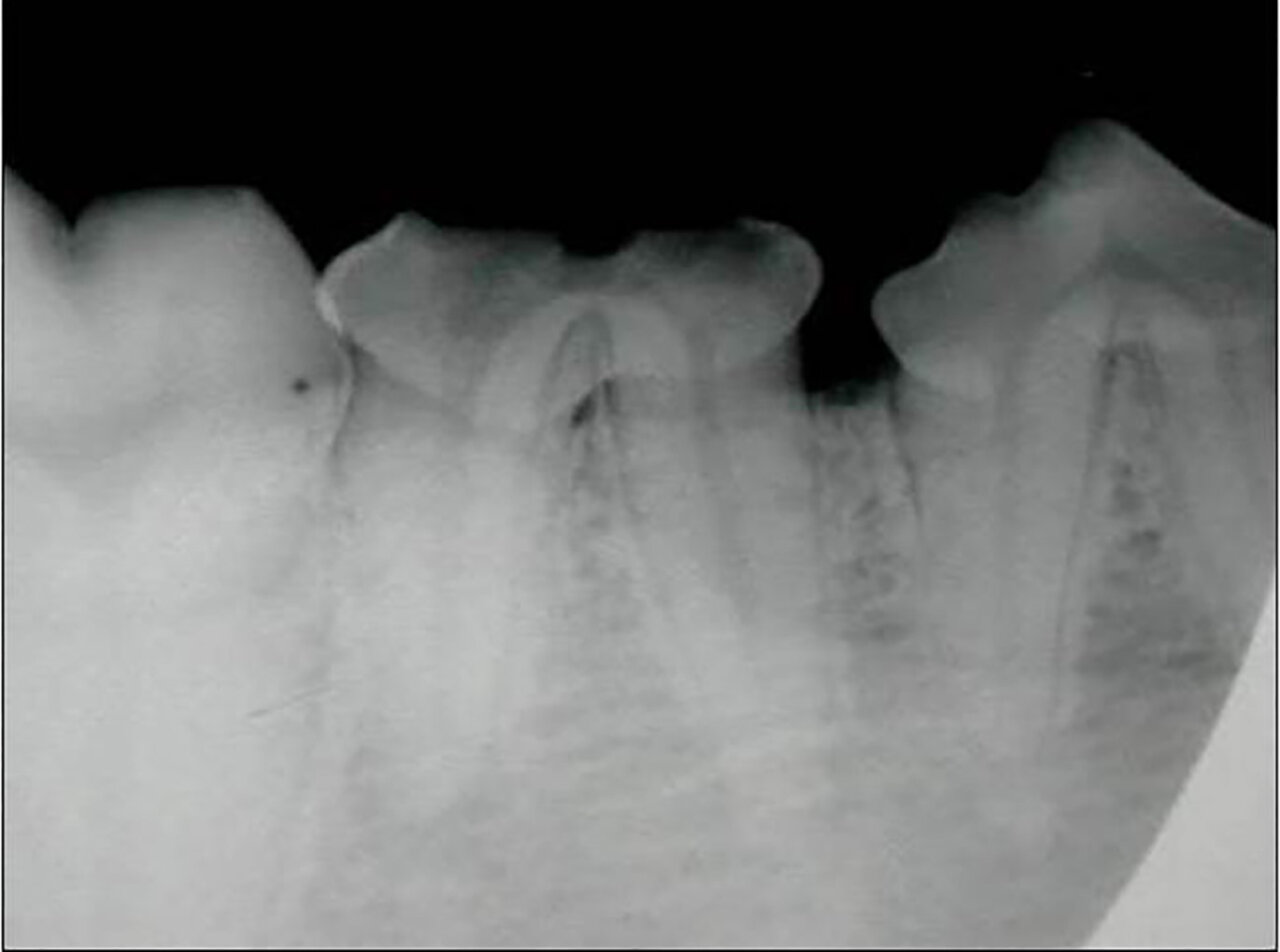

Alteración en el número y posición de los dientes

Ausencia dental

Cuando en una exploración visual de la boca observamos una ausencia dental debemos hacer una radiografía que nos indique la causa, que puede ser de origen genético o deberse a alteraciones sufridas durante las primeras etapas del desarrollo dental o a lo largo de la vida del animal.

A nivel radiológico nos podemos encontrar con varias situaciones:

- Ausencia del diente porque no se ha formado (agenesia).

- El diente no ha erupcionado por estar ectópico (fuera de su área anatómica).

- El diente está incluido o impactado (cuando no logra erupcionar o lo hace parcialmente por diferentes causas).

También puede ser debida a la pérdida dental (por EP, por ejemplo) o a fracturas de corona en las que quedan restos de estructuras dentales bajo la encía. Por tanto, dependiendo de ello, decidiremos el enfoque terapéutico que tomaremos en cada paciente con ausencia dental. (imágenes 14-17).

Aumento del número de dientes

La presencia de dientes supernumerarios también debe ser estudiada mediante la radiología intraoral. La causa principal es genética y la radiología nos permitirá valorar su naturaleza, si se trata de un diente definitivo o la falta de exfoliación de dientes deciduos (en caso de no tenerlo claro a la inspección visual). En este último caso, podremos valorar el estado de la raíz y su relación con el diente permanente, aspectos que debemos tener en cuenta a la hora de realizar su extracción (imágenes 18 y 19).